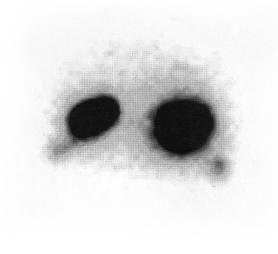

Непрямая лимфосцинтиграфия (НЛСГ) лимфатических узлов шеи основана на избирательном накоплении коллоидных частиц в РЭС-клетках лимфатических узлов. Радиофармпрепарат Тс-99 (Россия) характеризуется быстрым распространением по лимфатическим путям. Специальной подготовки больного не требуется. Радиофармпрепарат (РФП) нами вводился под слизистую основания опухоли в объеме 0,5 мл, а также в здоровую сторону. Сцинтиграфия выполнялась дважды, через 3 и 6 часов после введения радиофармпрепарата. Основной вид анализа – визуальная оценка сцинтиграмм. При этом учитывались топография, форма, четкость контуров лимфатических узлов, а также степень накопления в них радиофармпрепарата.

При введении РФП в край корня языка, в этой области, вследствие обилия лимфатических сосудов, выведение коллоидных частиц происходило более быстро и в большем количестве, чем при других способах введения. Через 24 ч в области введения оставалось не более 40 % радиофармпрепарата, тогда как остальные 60 % распределялись в регионарных лимфатических узлах (рисунки 4 и 5).

Рисунок 4 – Поражение метастазами яремно-двубрюшного узла слева (сцинтиграмма) | Рисунок 5 – Поражение метастазами подчелюстных лимфатических узлов (сцинтиграмма) |